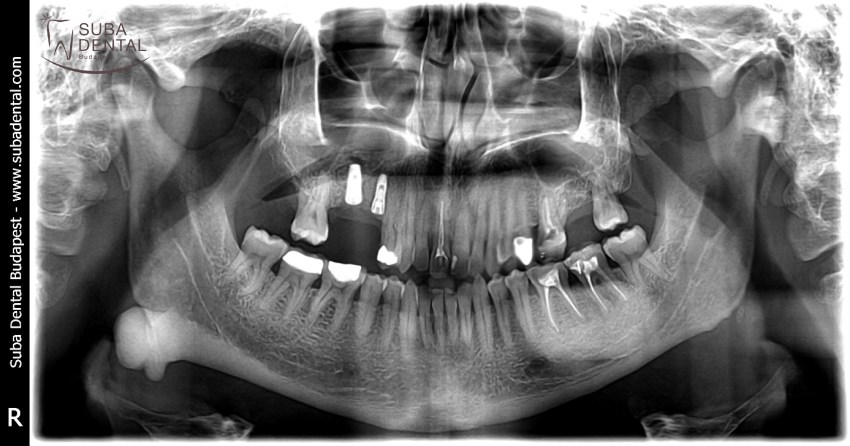

Panoramic radiograph of chronic dental foci, teeth affected by periodontal disease, and root remains. All teeth had to be extracted

Follow-up panoramic radiograph following the installation of implants. Our patient would have needed a bone graft but was completely inconvincible. Therefore, a total of 4 implants were installed per jawbone that would support a bar denture. The dental foci and infections totally destroyed bone width and bone height as a result of which the mounting of implants required great effort and could only be carried out in an asymmetric fashion.